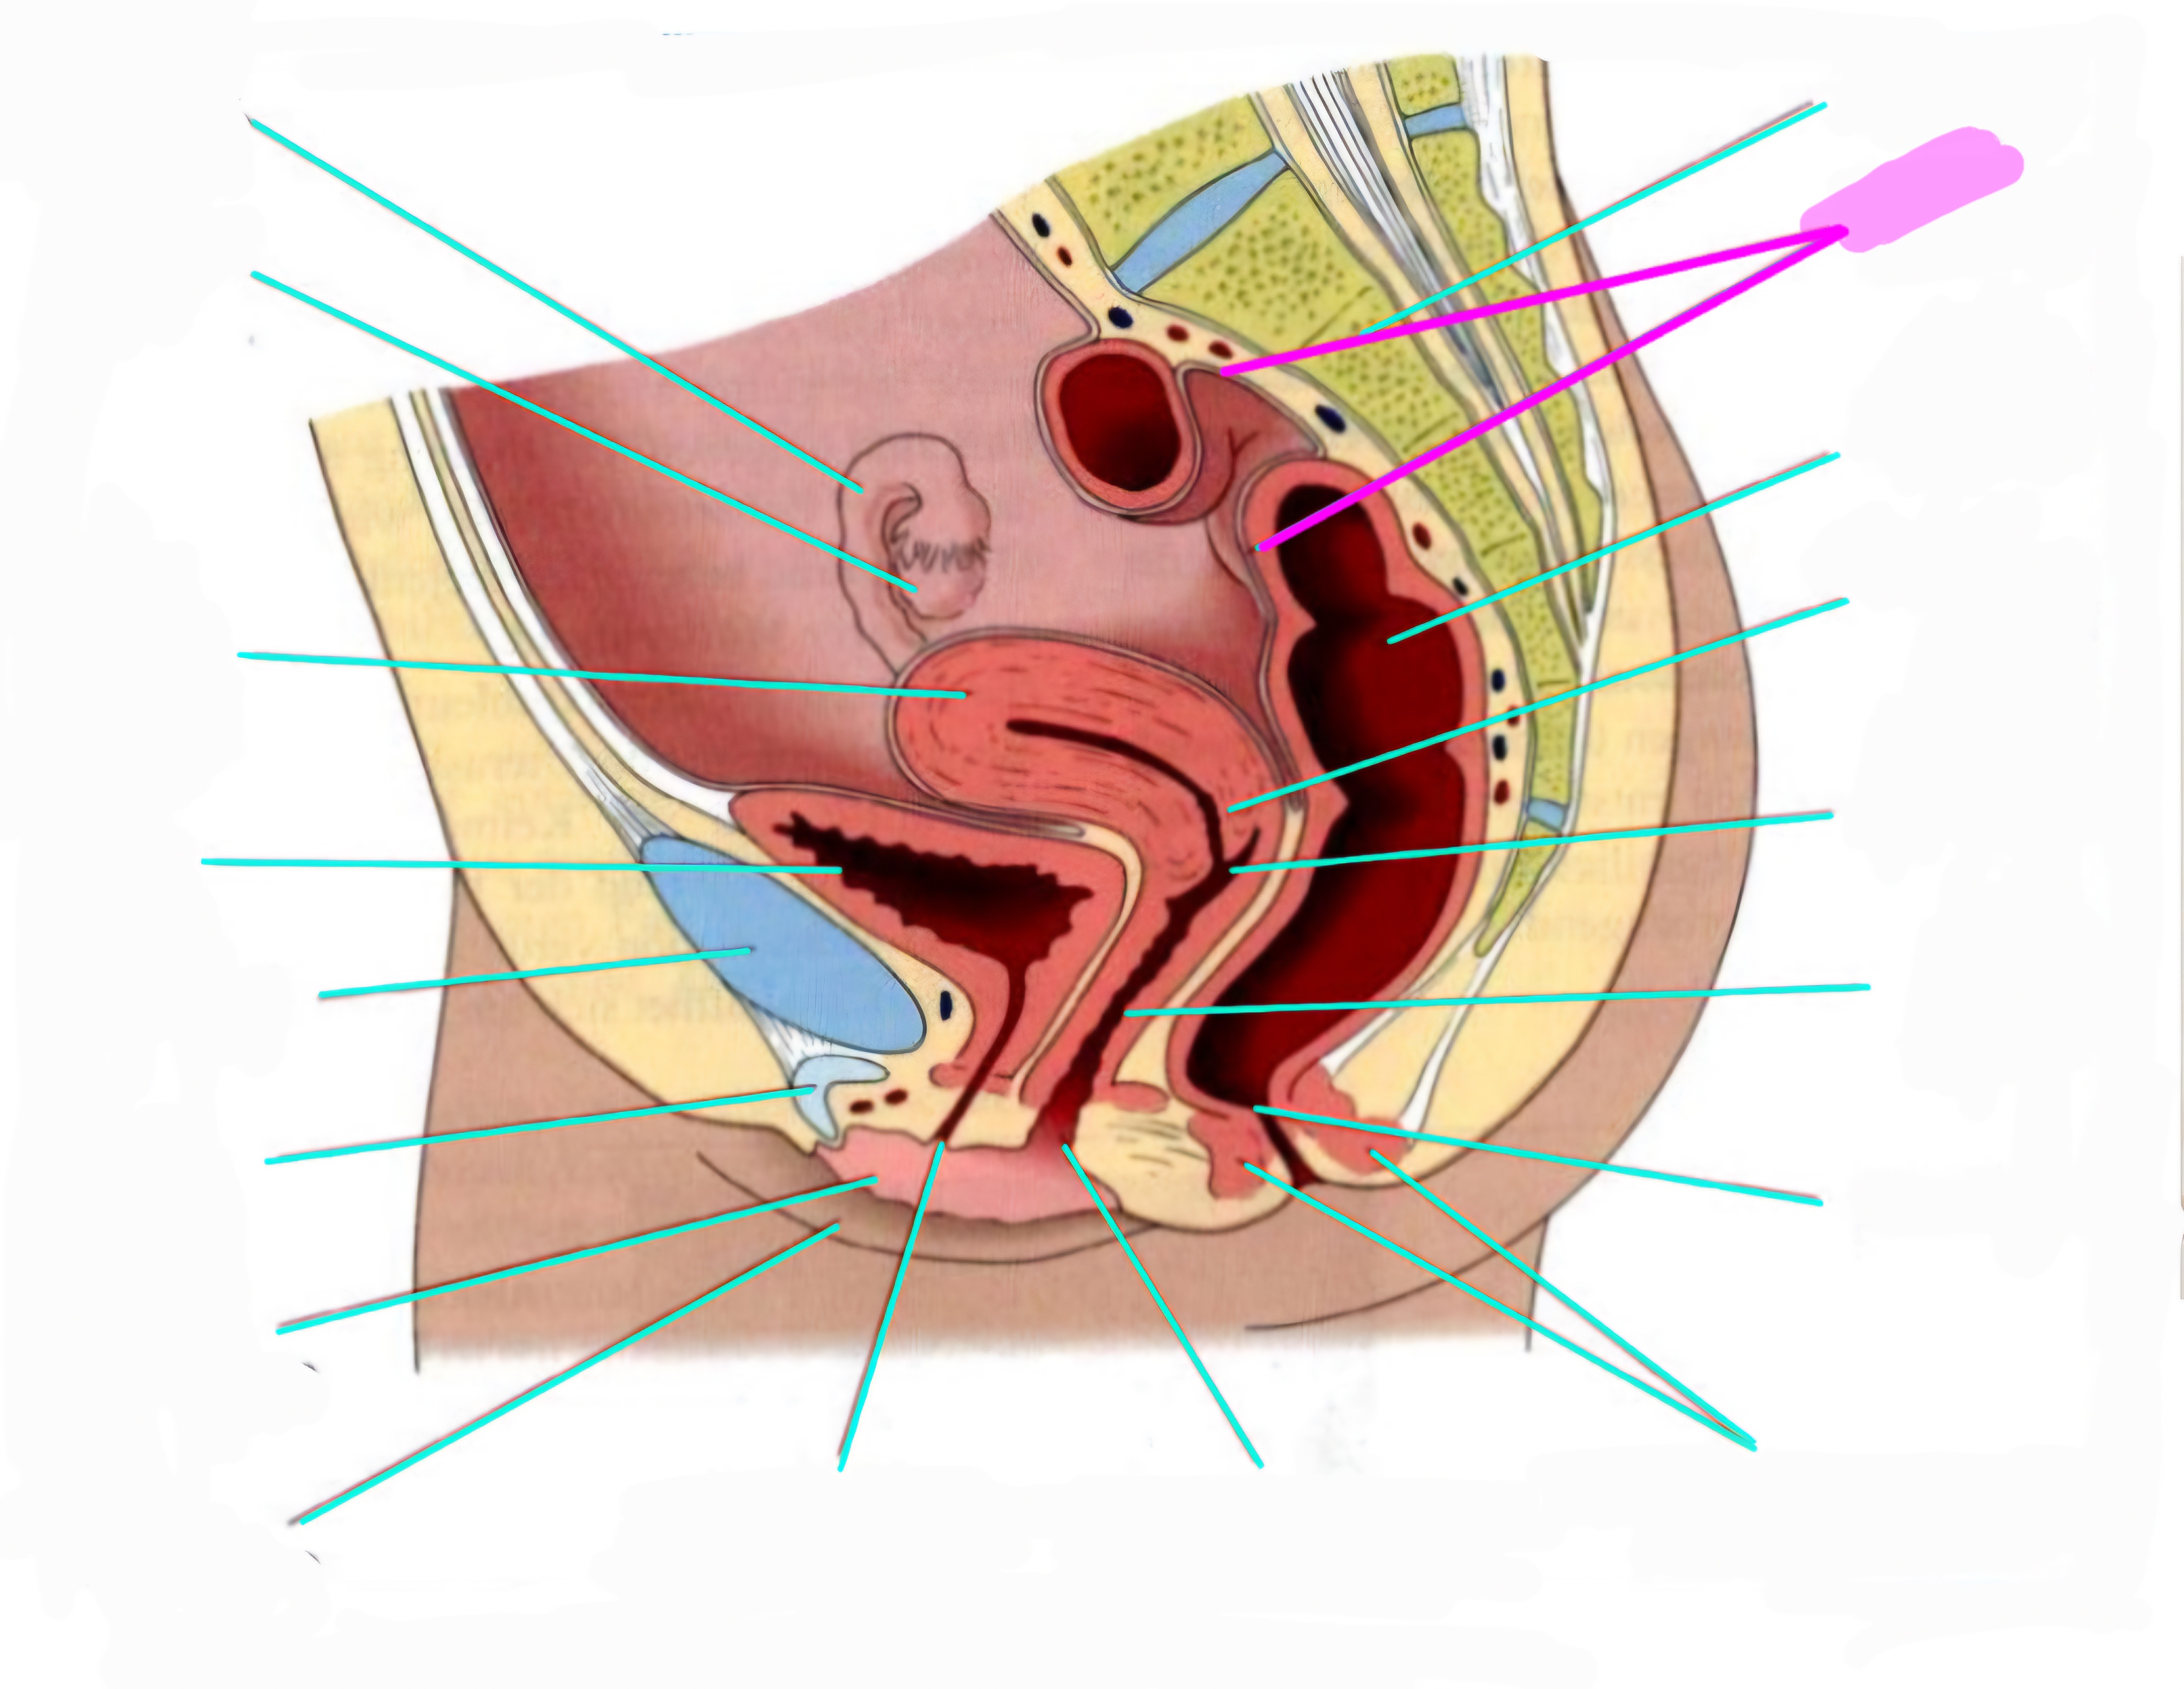

wbl. genital Anatomie

19 Terms

Tubea uterina (Eileiter)

Ovar (Eierstock)

Uterus (Gebärmutter)

Vesica Urinaria (Harnblase)

Symphyse

Klitoris

Labia minor pudendi (kleine schamlippen)

Labia Majoran pudendi (große Schamlippe)

Urethra (Harnröhre)

Introitus vaginae (Scheideneingang)

Sphincter ani externes (äußere Afterschließmuskel)

Anus (After)

Vagina (Scheide)

Portio (äußerer Muttermund)

Rektum (Mastdarm)

Zervix (Gebärmutterhals)

Peritoneum (Bauchfell)

Os sacrum (Kreuzbein)